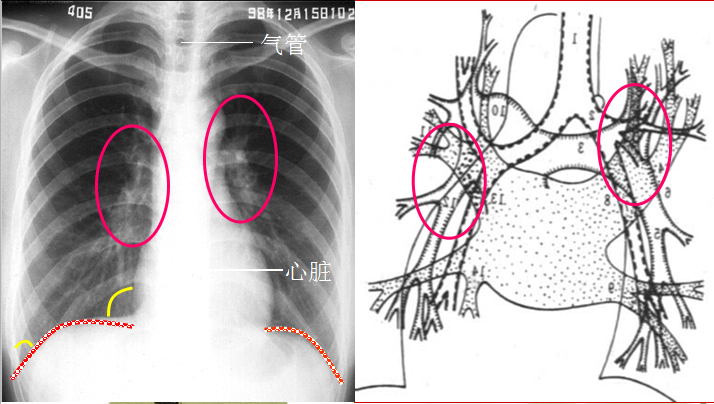

怎样阅读胸片 好网角收藏夹